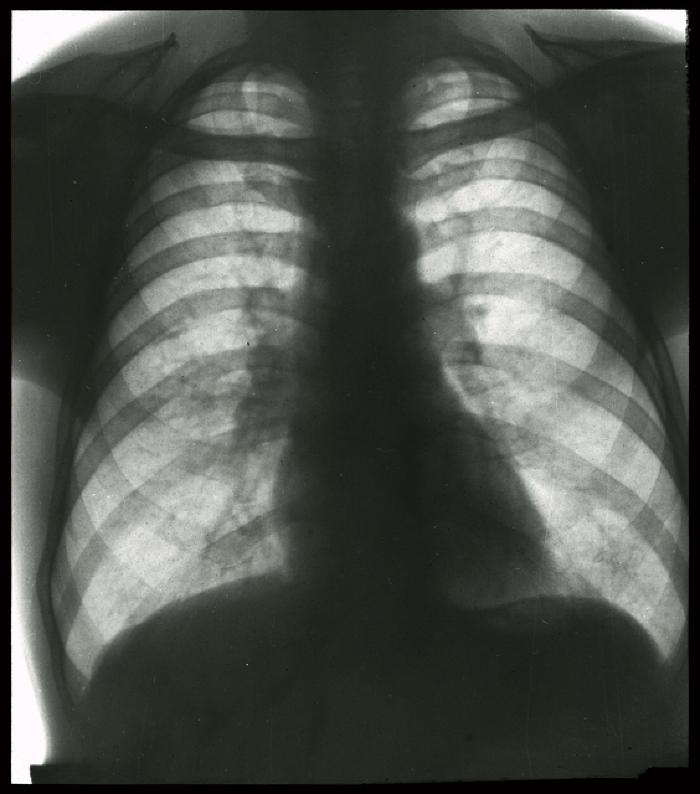

Document médical, radiographie de poumons non identifiés.